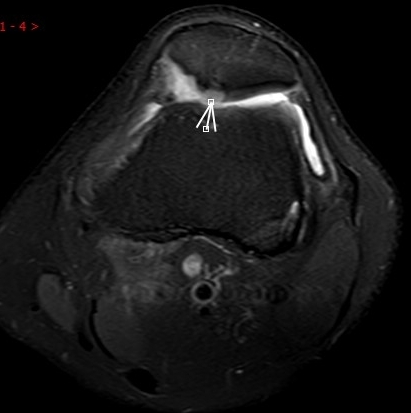

2. 運(yùn)動(dòng)后“打軟腿”——韌帶的“斷弦危機(jī)”

場(chǎng)景:打球急停后膝蓋不穩(wěn),走路像“踩棉花”

MRI偵查:揪出前交叉韌帶斷裂(呈“波浪狀”或連續(xù)性中斷)、內(nèi)側(cè)副韌帶損傷,防止關(guān)節(jié)“脫軌”

(內(nèi)側(cè)副韌帶損傷)